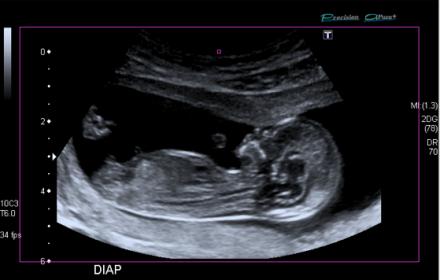

Boy or girl? Baby was measuring exactly 13 weeks.